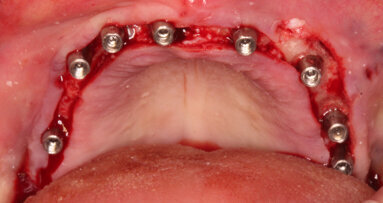

Nell’ultimo decennio la GBR è stata descritta come una tecnica efficace e predicibile per le rigenerazioni in senso verticale della mandibola. Questa tecnica si basa sull’utilizzo di una membrana per ricreare una spazio ben delimitato in cui coagulo e innesto di biomateriale possono stabilizzarsi, consentendo così la formazione di nuovo osso senza l’infiltrazione di cellule epiteliali e connettivali.

Studi clinici e istologici sull’uomo15-18 hanno successivamente dimostrato che aggiungere un innesto osseo di qualsiasi natura (autologo, omologo, eterologo o misto) al di sotto della membrana aumenta significativamente la rigenerazione ossea. L’efficacia e la predicibilità della GBR furono successivamente confermate da uno studio prospettico di Simion19 su 123 impianti. I risultati dimostrarono che gli impianti posizionati nell’osso rigenerato rispondevano ai carichi masticatori nella stessa maniera degli impianti posizionati in osso nativo.

In questo articolo vengono descritti i passaggi salienti della tecnica GBR.